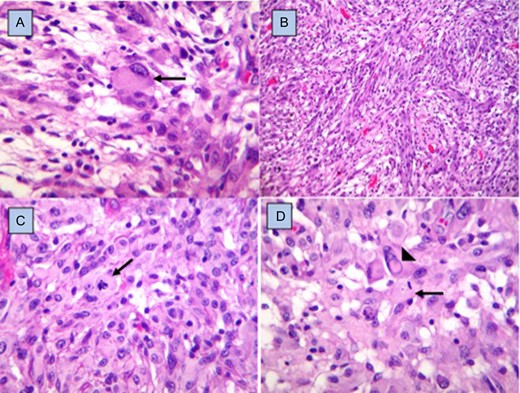

The histopathological study showed anaplastic astrocytoma. In the immunohistochemistry reactions, there was intense positivity for the glycoprotein acid protein, negativity for the epithelial membrane antigen, a Ki67 with a proliferation index of 5% and a p53 positive in 30% of the neoplastic cells (Fig. 3).

Histopathology. Fibrillar matrix with pleomorphic cells, some with gemistocytic appearance (arrow) (A), alternating with areas of spindle cells arranged in interlaced fascicles (B), and round cells with epithelioid appearance (C), with mitosis figures (arrows), as well as others with nuclear atypia and pseudointranuclear inclusions (arrowhead) (D). Hematoxylin and eosin staining, ×40.